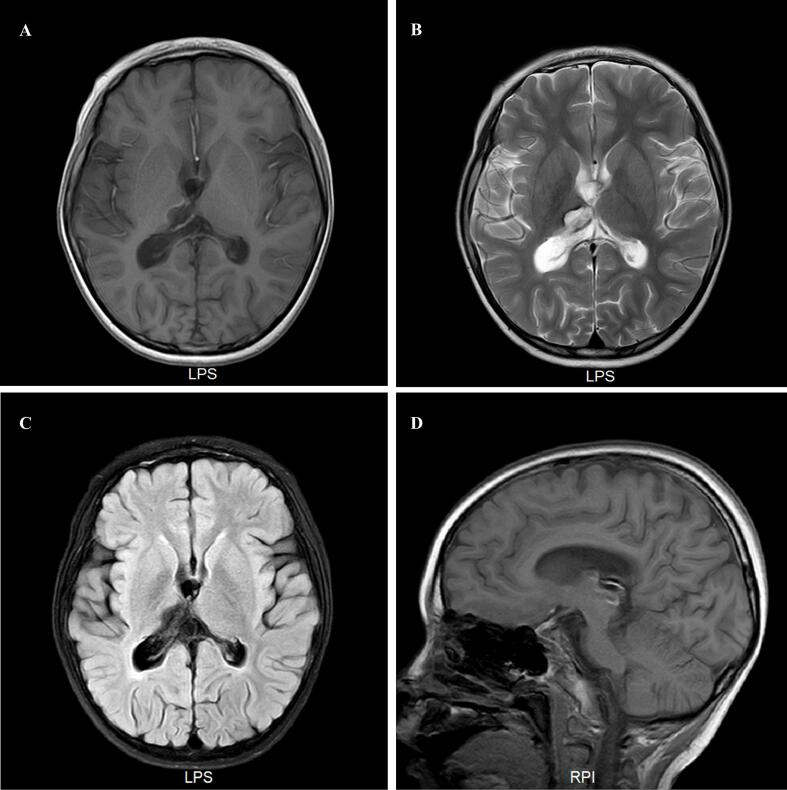

We presented a 7-year-old boy with refractory Epileptic Encephalopathy with Spike-and-Wave Activation in Sleep (EE-SWAS) successfully managed with a combination of propofol and midazolam. His seizures began at age 2, initially controlled by multiple antiseizure medications (ASMs) for almost three years. At age 5, seizures recurred with electroencephalography (EEG) showing electrical status epilepticus in sleep (ESES) and a spike-wave index (SWI) of 85 %. High-dose methylprednisolone pulse therapy initially reduced the SWI to 50 %, but it relapsed to 80 % within six months. Despite further treatments, including methylprednisolone, midazolam infusion, and four combined ASMs, the SWI persisted between 75 % and 85 %, leading to progressively worsening cognitive impairment and subsequently a somnolent state with nearly continuous discharges. During hospitalization, a combination of propofol and midazolam significantly improved the condition, reducing the SWI to 50 % upon completion of the treatment period. Over a three-year follow-up, no ESES or seizures were reported, and cognitive function notably improved. Currently, there is no consensus on the treatment of ESES, which is sometimes refractory to medication and can result in partially irreversible cognitive impairment. Propofol in combination with midazolam has demonstrated effective suppression of ESES phenomena, presenting a promising treatment strategy for refractory ESES.